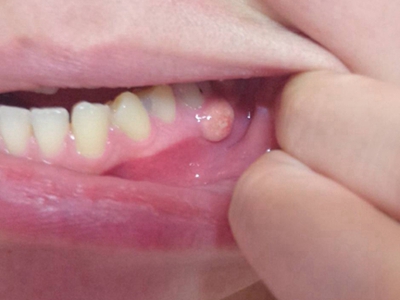

牙龈瘤多发于女性,以青年及中年人为常见,多发生于牙龈乳头部,位于唇、颊侧者较舌、腭侧者多,最常见的部位是前磨牙区。肿块较局限,呈圆形或椭圆形,有时呈分叶状,大小不一,直径由几毫米至数厘米。

肿块有的有蒂,如息肉状;有的无蒂,基底宽广,生长较慢,但在女性妊娠期间可能迅速增大。较大的肿块可以遮盖一部分牙及牙槽突,表面可见牙压痕,易被咬伤而发生溃疡,伴发感染。随着肿块的增长,牙槽骨壁逐渐被破坏,牙可能发生松动、移位。